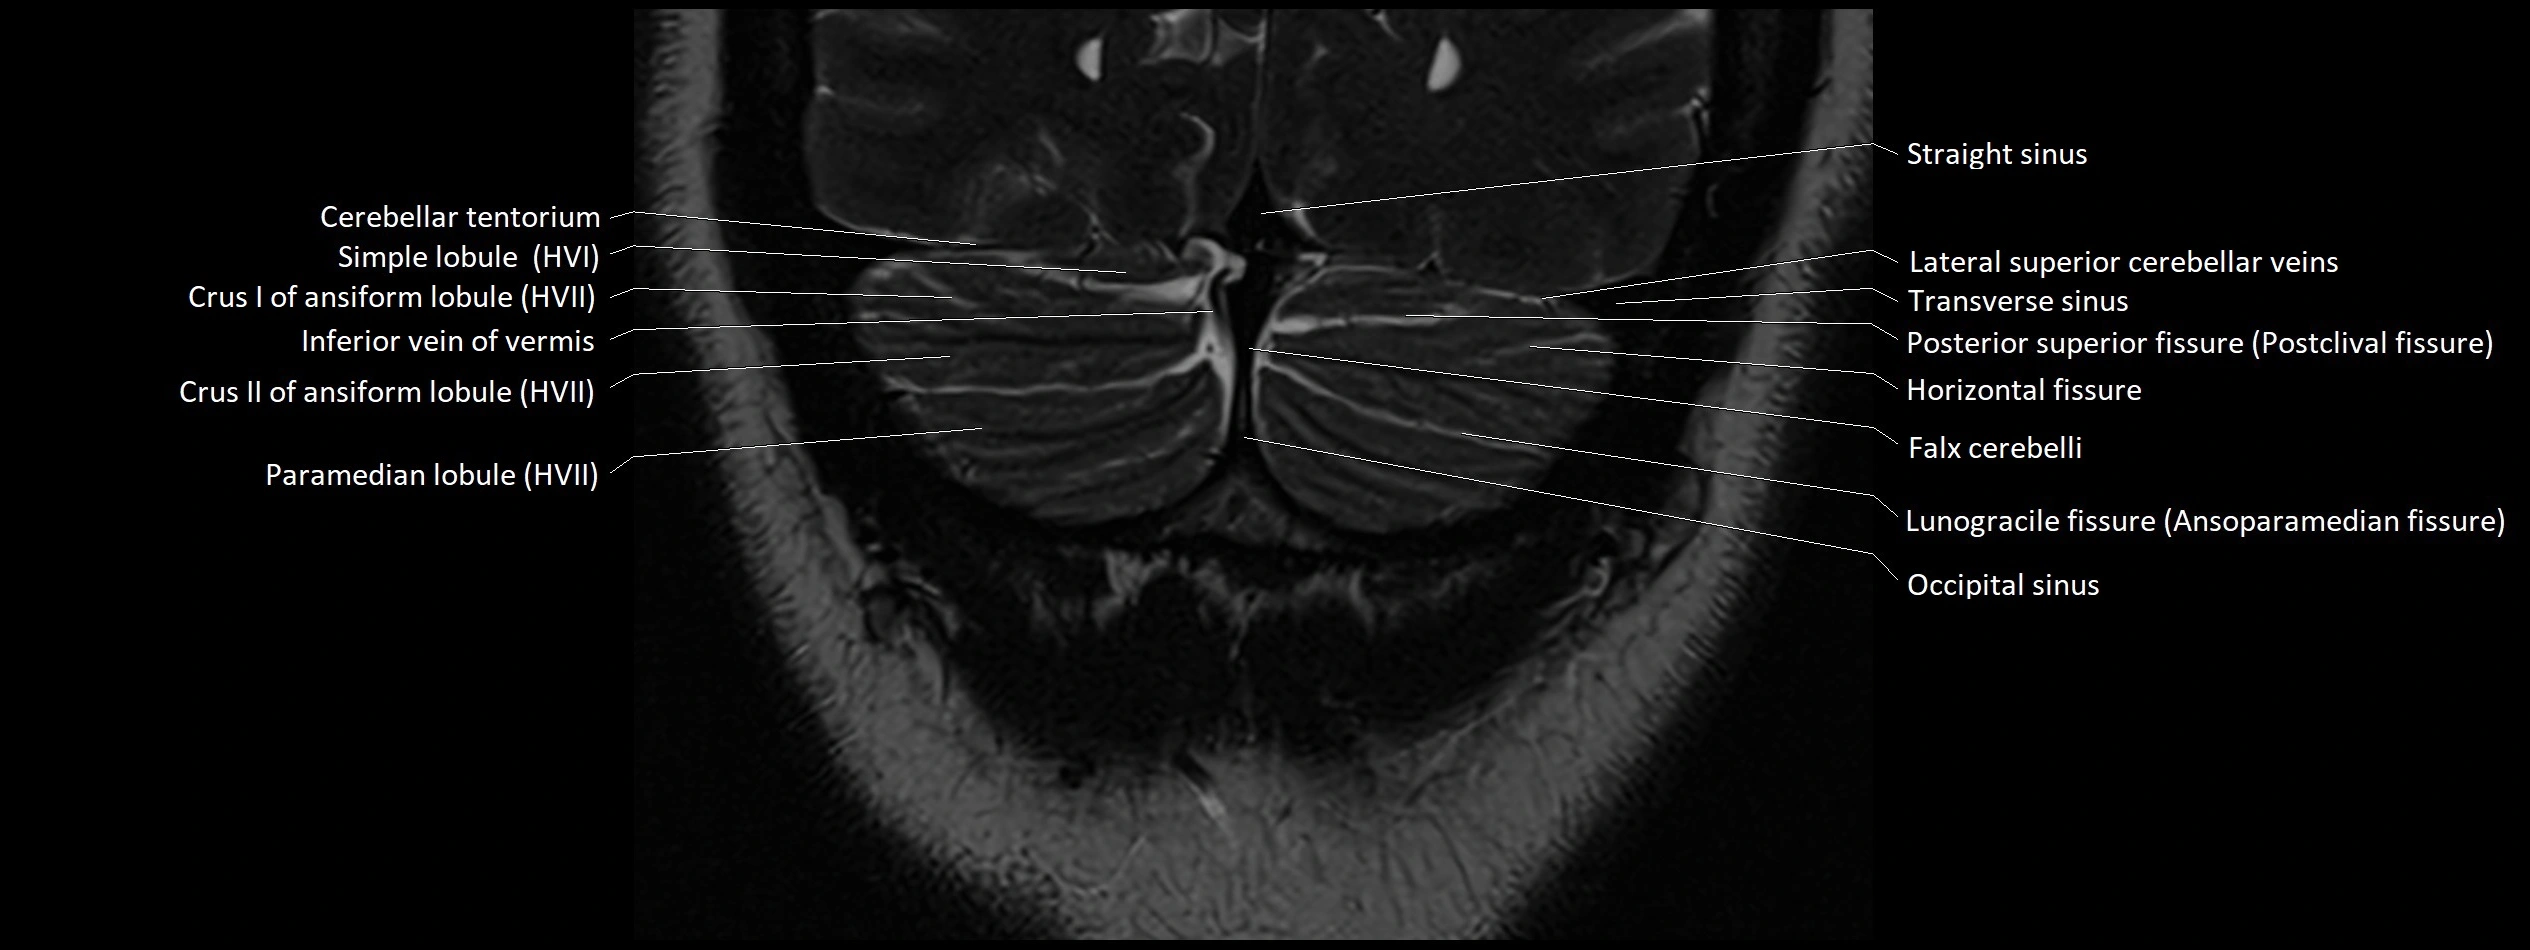

- Horizontal fissure (cerebellum)

- Inferior vein of vermis

- Lunogracle fissure

- Lunogranicile fissure of cerebellum

- Occipital sinus

- Paramedian lobule

- Paramedian lobule (HVII) of cerebellum

- Posterior superior fissure

- Simple lobule

- Simple lobule (HVI) of cerebellum

- Straight sinus

- Superior cerebellar vein

- Superior hemispheric cerebellar veins

- Superior hemispheric veins of the cerebellum

- Transverse sinus